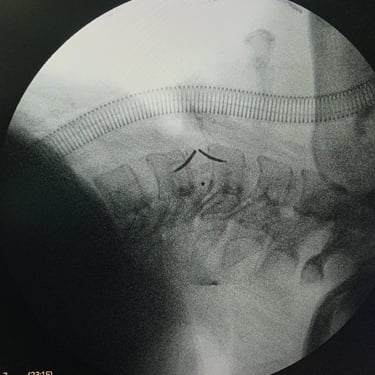

Hernia cervical – Cirugía de discectomía con artrodesis (ACDF)

La hernia cervical es una causa frecuente de dolor en el cuello, hormigueo en los brazos y debilidad muscular. Cuando el tratamiento conservador no alivia los síntomas, la cirugía de discectomía cervical con artrodesis (ACDF) se convierte en una excelente alternativa. Este procedimiento consiste en retirar el disco dañado que comprime los nervios y reemplazarlo con un injerto o prótesis que estabiliza la columna. La ACDF ofrece alta tasa de éxito, mejorando el dolor, la fuerza y la calidad de vida. Gracias a técnicas modernas y una recuperación controlada, muchos pacientes vuelven rápidamente a sus actividades habituales.